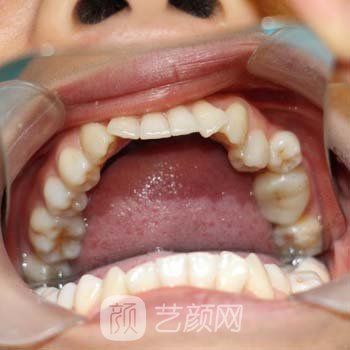

在我去廊坊市人民医院整形科做牙齿矫正手术之前,我的牙齿拥挤而歪斜,较为不整洁。因为牙齿长得丑,我一直不敢笑。我性格开朗性感,变得有点内向。看着别人整齐洁白的牙齿,我无比羡慕。经过长期的思想斗争,我仍然选择去医院为牙齿矫正做手术。

来医院后,我有点紧张。医院的环境温暖干净,医护人员较为热情。护士带我去了医生的办公室。医生人很好,和他交流很愉快。根据我在牙齿,的情况,医生说我可以在矫正戴牙套

然后推荐了几款牙套,因为刚开始工作,手里没有多少钱,所以选择了经济型金属支架牙套。刚戴上牙套的时候,我的牙齿很不舒服,拒绝了这个异物。适应了一个星期,好多了。

戴了这个牙套一年半,我成功摘下来了。牙齿如她所愿变得美丽。这是我在矫正,牙齿的整个运营经历,自从我的牙齿变得美丽,我的运气有所改良,我的业绩一直在上升。老板很赏识我,提拔我为部门经理。哈哈,我厉害吗?